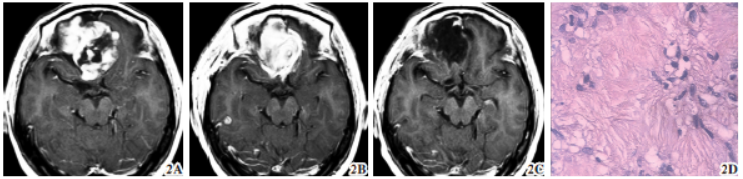

病例2(图2):女性,40岁;因“反复肢体抽搐10年”入院。外院脑电图检查

未见异常,给予抗癫痫治疗后,症状无明显缓解。近2个月频繁出现颜面部抽搐,肢体抽搐加剧,故入院治疗。入院查体:双侧瞳孔等大,对光反射灵敏,视野正常,视力

稍下降,嗅觉减退。肌张力正常,双侧肌力Ⅴ级。

入院头颅CT显示右侧额叶类圆形占位,跨越中线,呈等、低密度,可见骨质破坏。头颅T1WI示病灶呈低、等信号,可见囊变,T2WI为不均匀高信号。术前诊断:右额叶占位,同上述额下入路开颅,但切口跨中线3~5cm。处理右侧占位后,继续切开大脑镰下缘,暴露对侧肿瘤,完整切除对侧占位,修补颅底。

送检组织在高倍镜下呈H-W菊形团样分布,细胞核小而均匀,核深染并可见部分核分裂,部分见灶性坏死。Ki-67指数为15%,其余免疫组化指标同上。术后诊断为右侧ONB,术后1周复查头颅MRI示肿瘤全切,肢体抽搐明显改善,但嗅觉减退未好转。术后随访5年,MRI检查未见复发。

图2 女性右侧ONB。2A 术前MRI T1WI 示额底肿瘤骑跨大脑镰生长,不均匀强化,内可见囊性小腔;2B 术后T1WI示肿瘤全切除,但水肿

明显;2C 术后5年T1WI示肿瘤未复发;2D 病理示形态一致异型细胞环状排列,呈H-W菊形团样分布(苏木精-伊红染色× 400)